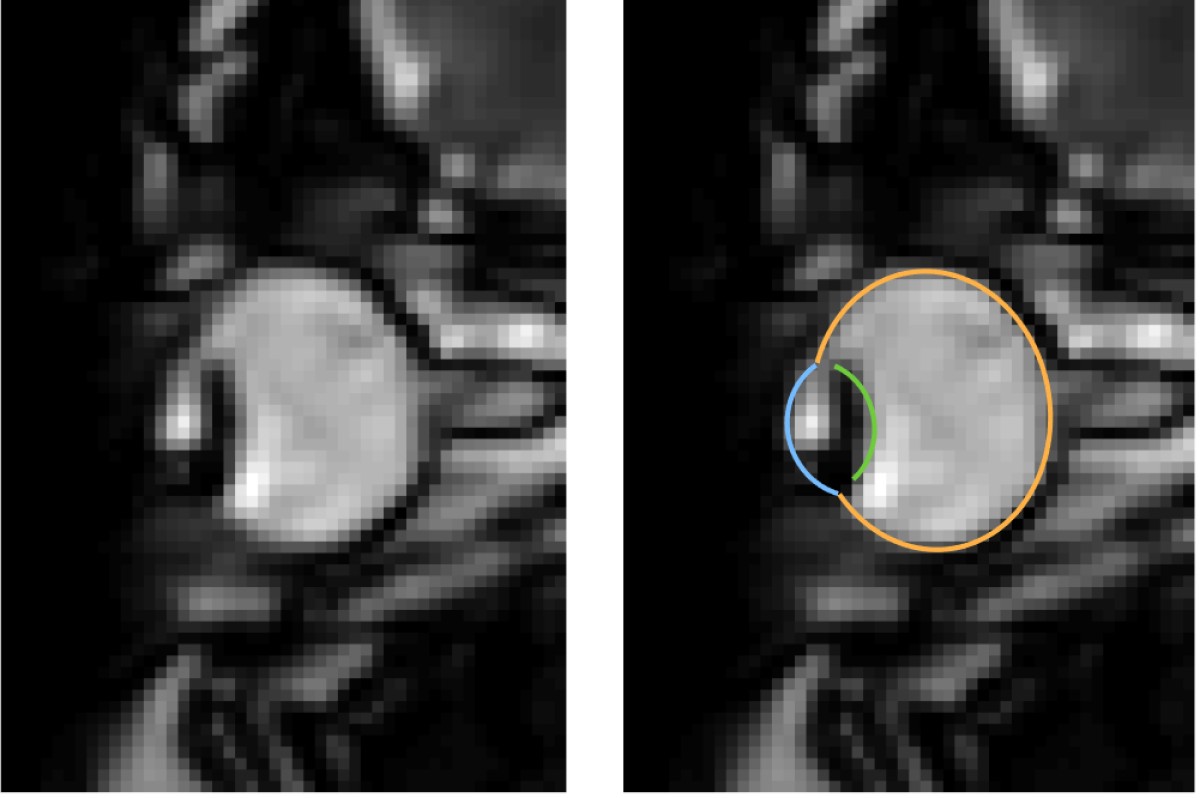

MRI images of eye movements during blinking: The eye is pulled back into the eye socket. The left image shows only the dynamic MRI data, the right image additionally shows the segmentation of the eye by the MREyeTrack. The photo corner consisting of six images shows the eye movement.© WWU - Johannes Kirchner

MRI is a relatively slow procedure, the temporal resolution usually ranges between seconds or minutes. Eye movements on the other hand are fast and typically last only a few dozen milliseconds. Recent technological advances allowed the recording of 2-D MR images at a resolution of up to 20 milliseconds. Those ultrafast MR sequences were initially developed for cardiac imaging and haven’t been applied to the recording of eye movements. “We could reach a temporal resolution of 35 milliseconds. Total scan duration of only a few minutes already leads to the acquisition of over 10000 images. For actual eye-tracking, a fully automatic segmentation algorithm to analyse these images was needed”, explains co-author Prof. Markus Lappe, professor for cognitive neuroscience at the Institute of Psychology at the University of Münster. “With ‘MREyeTrack’ we have developed such a segmentation algorithm, which allows the fully-automated analysis of eye position and orientation in every single image.”